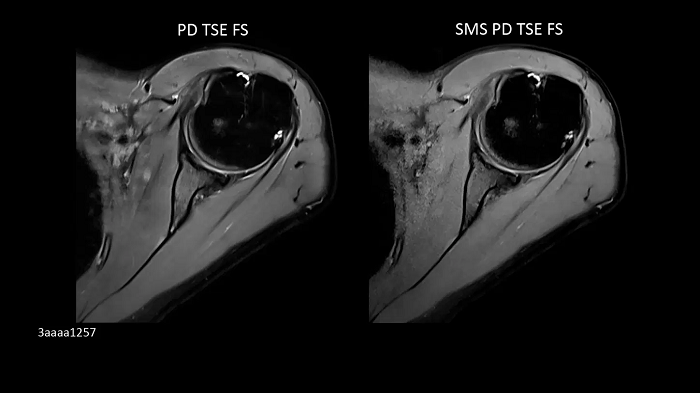

Shoulder imaging

Shoulder Shape 16 coil with patient-adaptive design enables Simultaneous Multi-Slice scan acceleration.

Left:

PD TSE FS | PAT 2 | 0.4 x 0.4 x 3.0 mm3 | TA 4:06 minutes

Right:

SMS PD TSE FS | PAT 2 SMS 2 | 0.4 x 0.4 x 3.0 mm3 | TA 3:08 minutes

Image Credit: Radiologie München Harlaching, Munich, Germany